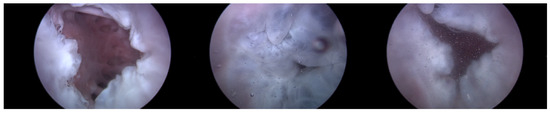

Endoscopic Image: During the experiment, the ability to adjust the intensity of TR using the TRG, as well as the changes made to the bpm, directly influenced the functionality of the TV. Real-time endoscopic imaging, as seen in Figure 6, was crucial in verifying the impact of these adjustments. This imaging technique allowed for the immediate observation of how alterations in the TR’s intensity or changes in the heart rate affected the TV’s performance. By providing a live visual feed, the endoscopic imaging enabled researchers to promptly ascertain whether the modifications being applied—either through the TRG or by adjusting the bpm—effectively influenced the valve’s operation. This real-time monitoring was essential for ensuring that the experimental conditions were accurately met and validating the immediate effects of these adjustments on the TV’s functionality.

As can be observed in Figure 8, up to a flow rate of 60 cc/min from the TRG, the TV of Heart 1 maintained its normal functionality. This was validated by the endoscopic images, as displayed in Figure 7. An induction of TR was discernible on elevating the flow rate to 70–80 cc/min; however, upon turning off the TRG, the TV reverted to its normal function. This behavior was consistent, reaffirmed by subjecting the system to the same conditions thrice, with 10 min intervals between each test. Figure 9 presents a cross-sectional view of the spectrum graph from Figure 8 during the normal phase, while Figure 10 illustrates a similar cross-sectional view but during the abnormal phase. The two figures show a noticeable discrepancy in the amplitude values between 50 and 100 bpm. Specifically, the maximum amplitude values differ tenfold, registering approximately 2.4 mmHg in the standard phase and 25 mmHg in the abnormal phase.

Figure 6. Endoscopic image of tricuspid valve function.

Figure 7. Endoscopic image of Heart 1 (valve open, normal valve closed, abnormal valve closed).